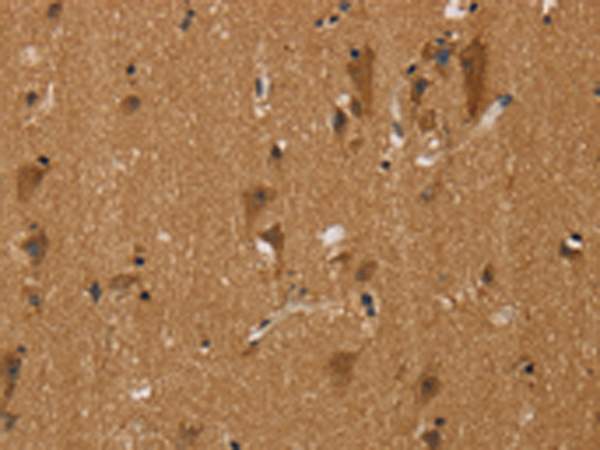

分类: 科研抗体货号: P08558别名: CI-13kA; CI13KDA; CI-13kD-A应用: IHC反应种属: Human, Mouse, Rat